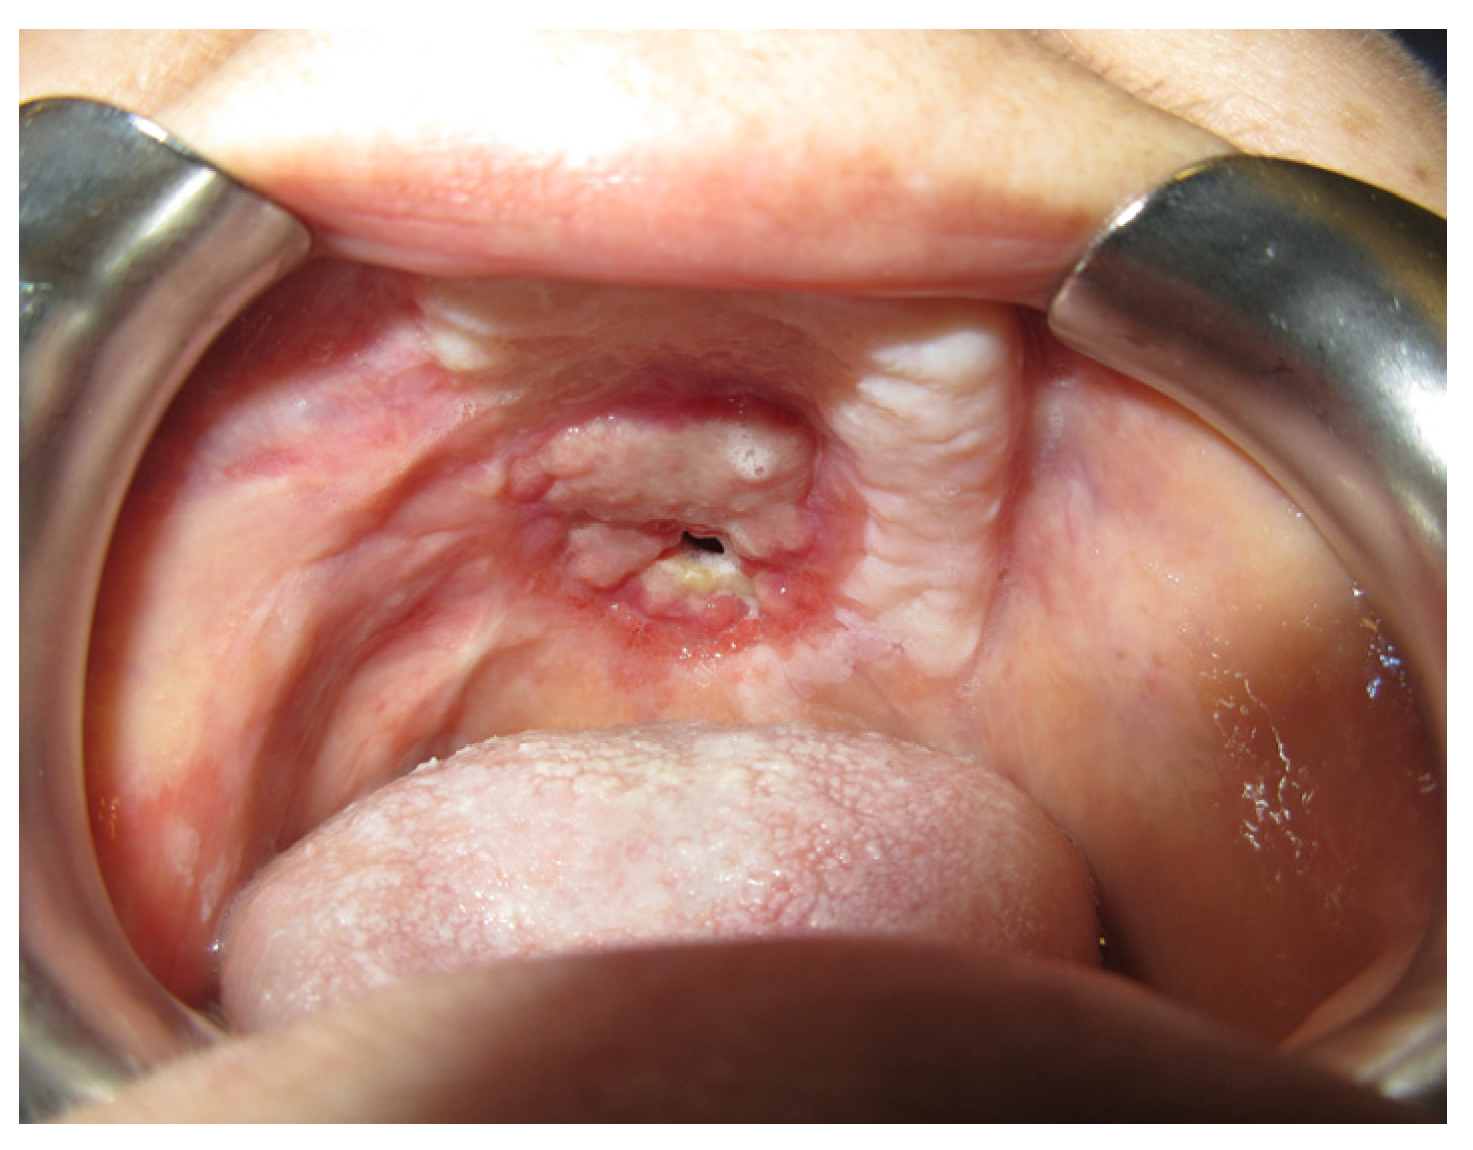

3.1.1. Case 1: A.R.

| A.R | X | * | 5 | 1 | ||